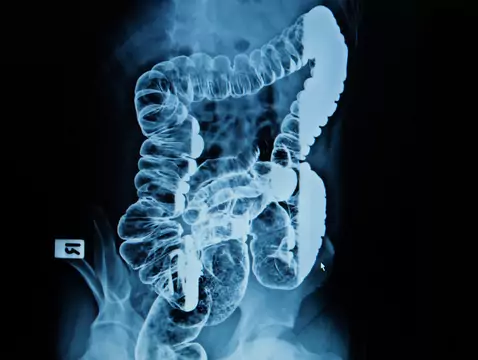

Der Weltkrebstag wird am 4. Oktober begangen. An diesem Tag lohnt es sich, die Menschen an die Bedeutung der Krebsvorsorge zu erinnern, damit wir schnell mit der Behandlung beginnen können und die Chance, den Krebs zu besiegen, viel höher ist.